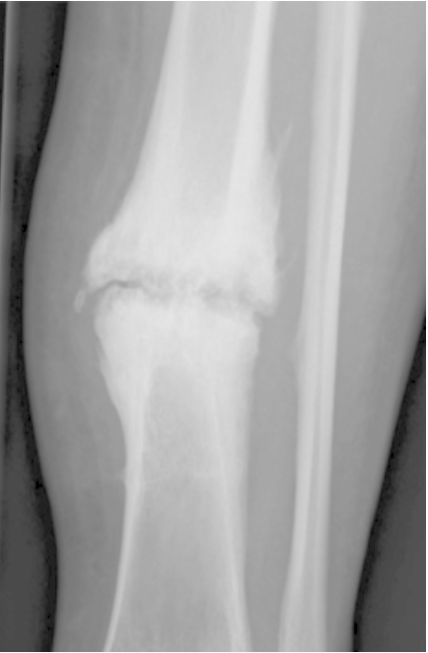

The given x-ray shows hypertrophic nonunion caused by inadequate _____